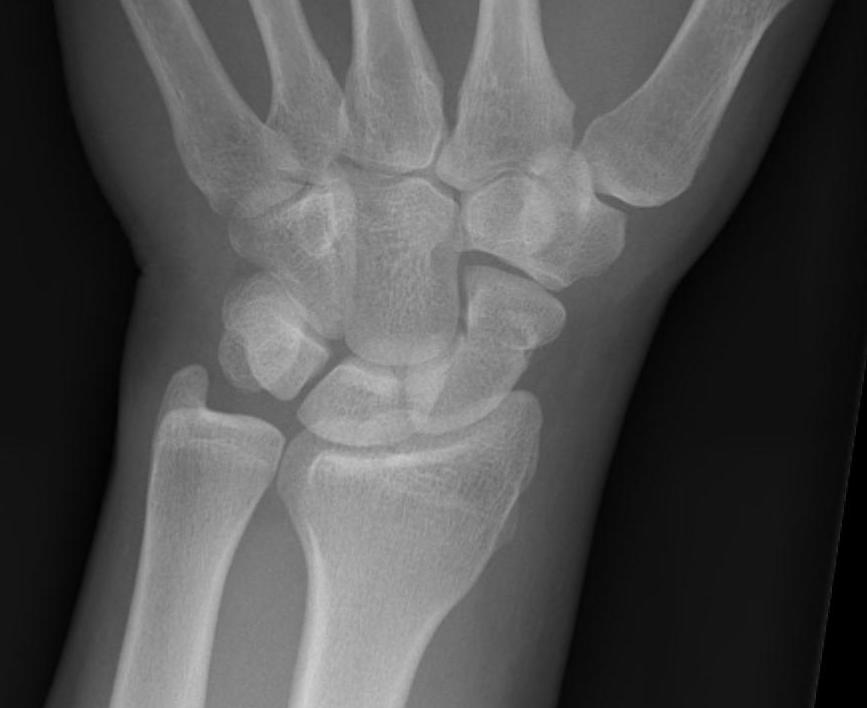

Scaphoid waist fracture 1 mm displaced

CT

Indication: any potential displacement

Instability

- displacement > 1mm on any film

- intra-scaphoid angle > 35o

- comminution

- proximal pole fractures

- perilunate trans-scaphoid dislocation